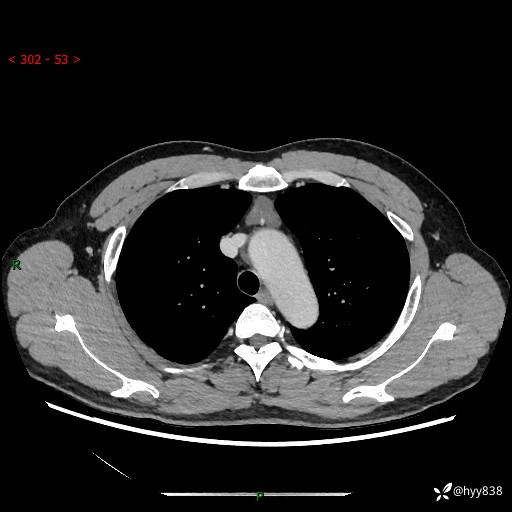

患者性别:女

患者年龄:49岁

简要病史:跟骨骨折,常规CT发现纵隔占位

胸部CT平扫

增强(动脉期+静脉期)